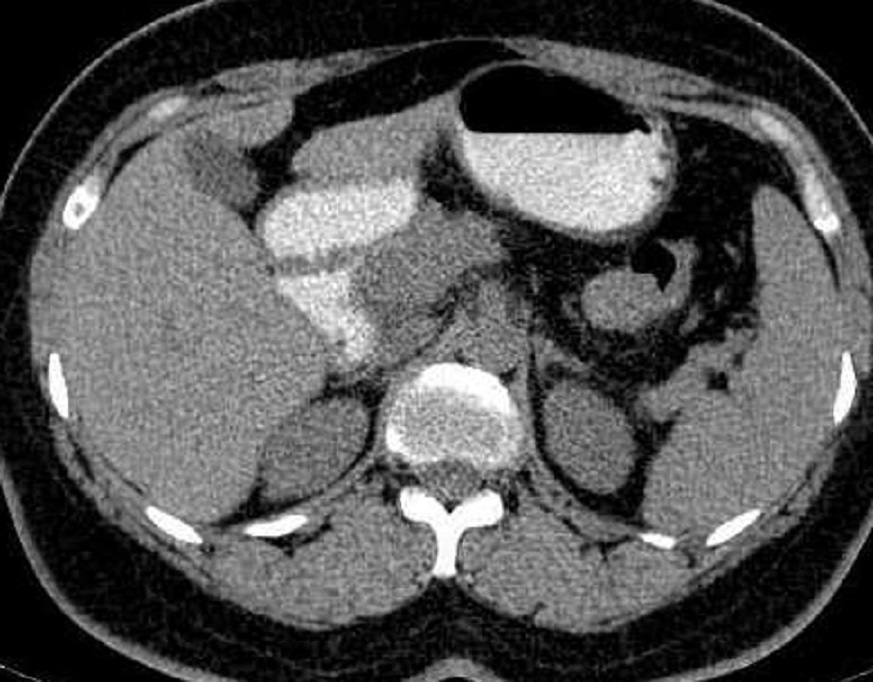

Image radiologique d'un

tumeur endocrine a petite taille du pancreas .

Aspect lesionnel TDM est une nodule isodense

du parenchyme pancreatique ( fleche rouge ) . Image

TDM en coupe |